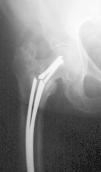

Estos dos sistemas abogan por síntesis rígidas, desechando la idea propuesta por Ender 5 , donde la elasticidad de la síntesis endomedular, asociada a la orientación en las tres direcciones del espacio dentro de la cabeza femoral, conseguía la estabilización y consolidación de estas fracturas (fig. 1).

Figura 1. Correcta posición en la cabeza femoral de los clavos de Ender en una fractura pertrocantérea.